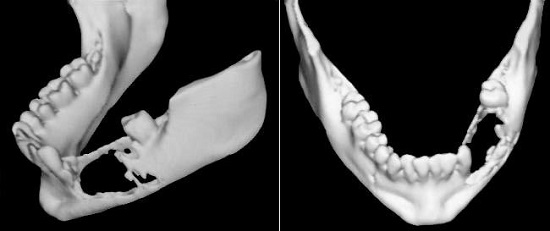

The three-dimensional reconstruction clearly illustrates the tumor extent, showing irregular bone resorption and destruction of the basal mandible (Figure 3).